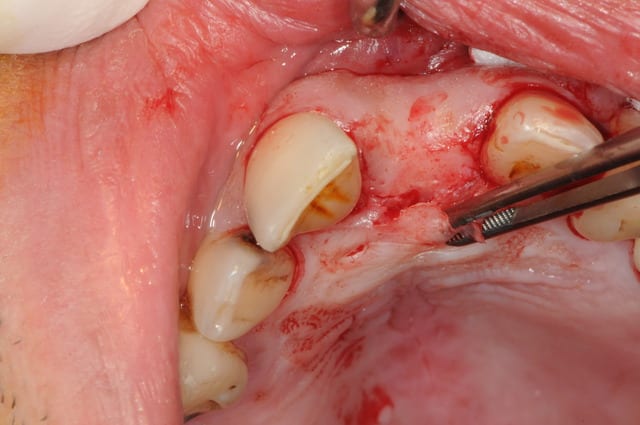

au cas où vous ne fait la provisoire immediatement, vous pouves choisir le" one stage procedure" . Dans ce cas, vous conservez la profile de la gomme avec une "gingiva former".

dans la zone estetique e tres important a fere extraction atraumatique e forage palatine pour preserver l os vestibularie.

le placement du implant doivent suivre( respecte) les règles de "3D insertion in estetic zone".

je vous recomendextraction avec la piezo.( piezotome satelec-est que ce j utilise)

prothèse définitive après 6 mois